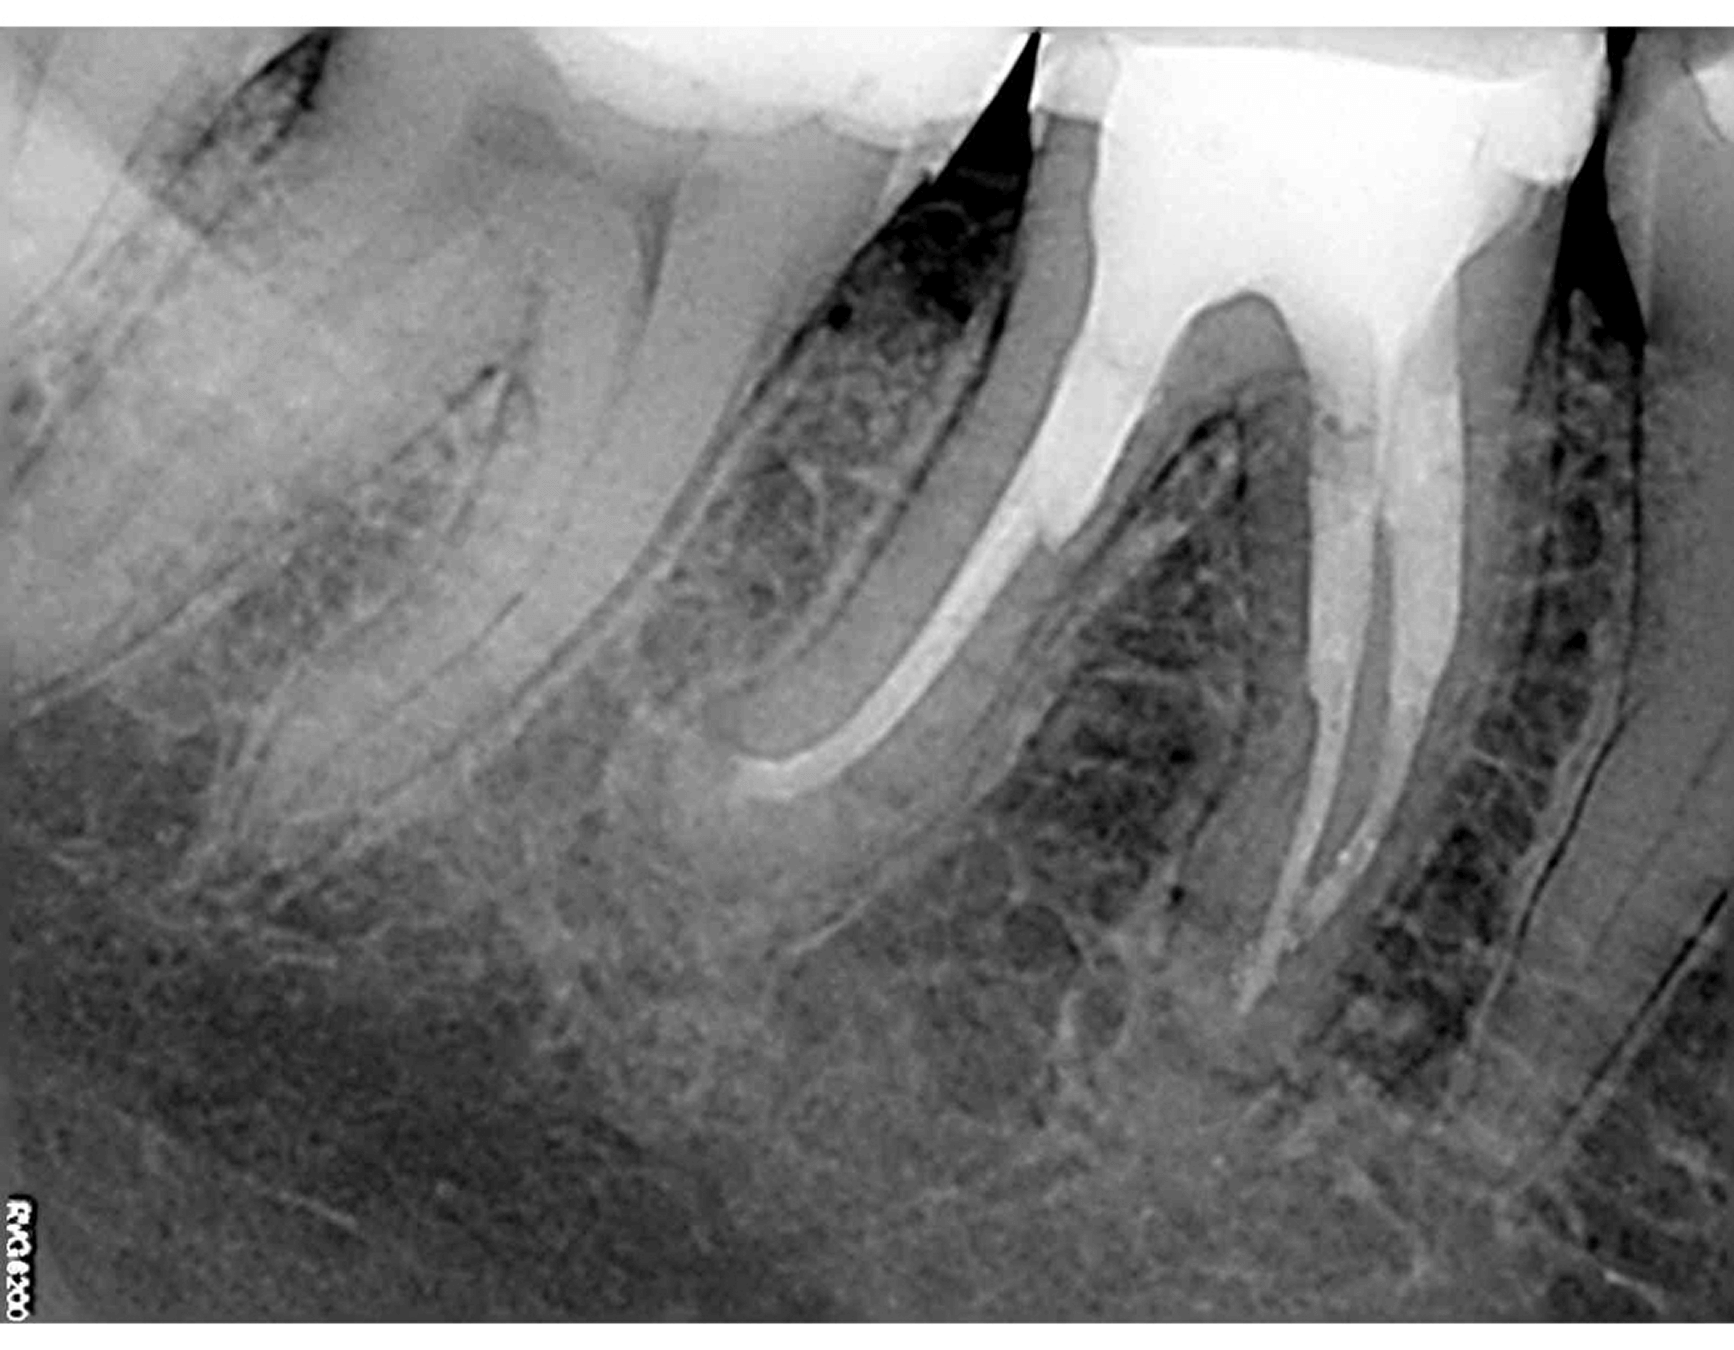

1. Исходная ситуация, зуб 46, апикальный периодонтит, в каналах мезиального корня сломаны два эндодонтических инструмента, устья перерасширены, в дистальном корне - два стекловолоконных штифта установленных в ступень не по оси канала. (Фото 1,2,3)